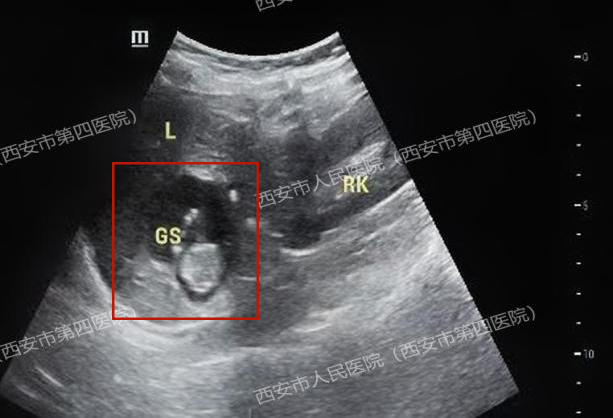

胎儿竟然长在了肝脏上!胎心搏动强劲有力,胎盘雏形也已形成,测量的顶臀径约36mm,估算的孕周近11周了!

肝脏妊娠的诊断需满足最为严格的标准:子宫内无妊娠囊、宫颈管内无妊娠物、双侧输卵管及卵巢正常,以及明确的腹腔内异位妊娠证据。

我院超声医学部与放射科通过高分辨率超声及上下腹部核磁共振(MRI)检查,结合患者血清HCG水平的动态变化,最终排除了子宫及附件妊娠,为后续治疗指明了方向。

受重力影响,受精卵多种植于腹腔内偏低部位,仰卧位时,肝右叶下表面相当于腹腔最低平面,便于附着,且肝包膜、肝实质血供丰富,利于胚胎的生长发育,因此,肝脏异位妊娠多出现在肝脏右叶下表面。